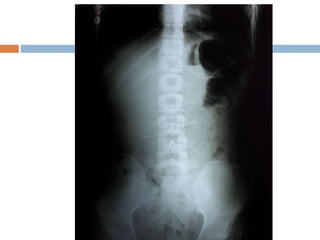

Initial Managment Initial managementof the patient involved intravenous fluid resuscitation, nasogastric tube insertion, Lab data , AP chest x-ray and Upright and Supine abdominal x-ray , abdominopelvic CT-Scan

 The initialchest radiograph performed in the ED was interpreted as showing a loculated air trapping on base of left hemithorax.

To identify thedefinite cause of the matter, CT-Imaging of the abdomen with oral and Iv contrast was performed which demonstrated left diaphragmatic rupture with herniation of viscus into the left hemithorax